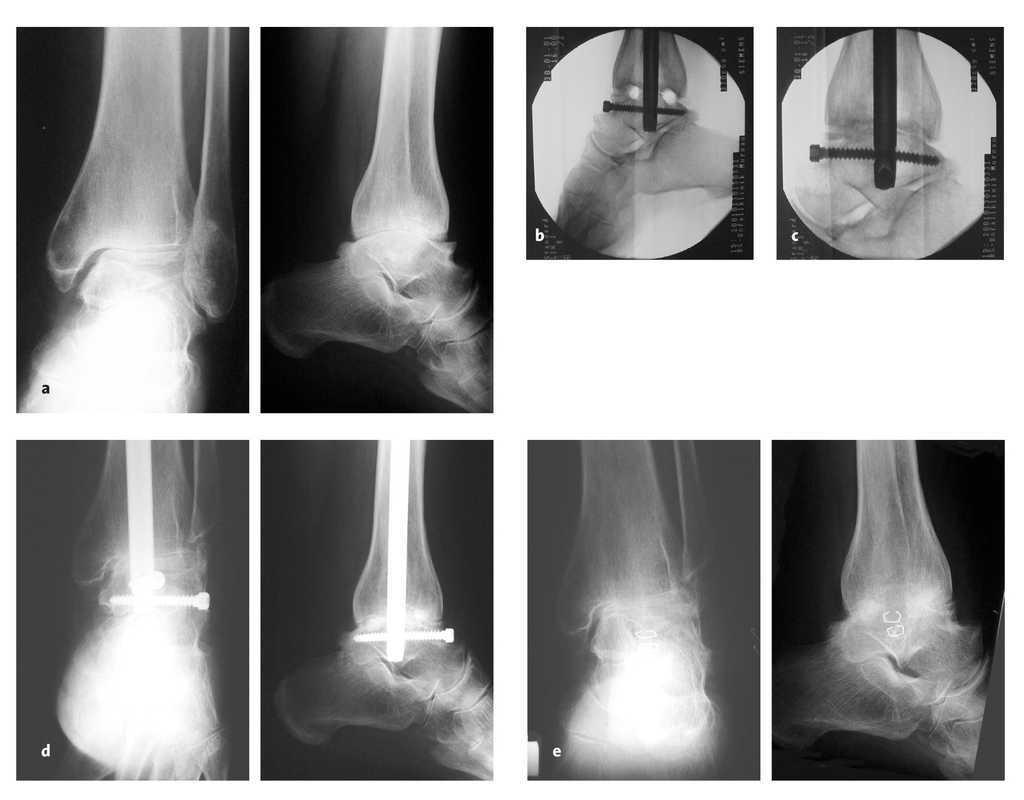

WebLaincapacidad permanente por artrodesises una situación médico – legal cada vez más frecuente en el momento de reclamar la declaración de nuestro grado de. WebEn función de ello, el grado de minusvalía por artrosis de rodilla puede ir desde un 7 a un 50%, debiendo tenerse especialmente en cuenta si la artrosis de rodilla afecta a los. WebSi se ha diagnosticado artrosis de rodilla a una persona, se le puede asignar un grado de minusvalía para ayudar a determinar el nivel de discapacidad y los beneficios a los que. WebUn grado de minusvalía es una designación legal que se usa para describir el impacto que una discapacidad o enfermedad tiene en la vida diaria de una persona. Los. WebLa artrodesis total de muñeca, también conocida como fusión de muñeca, es un procedimiento quirúrgico en el que se estabiliza o inmoviliza la articulación de la. WebEn el caso de que la artrosis afecte a una sola articulación, se suele otorgar una minusvalía del 10%. Si afecta a más de una articulación, el grado de minusvalía puede. Web¿Cuáles son los grados de minusvalía por artrosis? GRADO 0: NORMAL – En el grado 0 o normal, no existe ningún tipo de dolor, ya que se considera que se encuentran en este. WebEl grado de discapacidad por artrosis de rodilla o el grado de minusvalía por artrosis de cadera, por ejemplo, depende de las circunstancias que te exponemos. Sólo.

WebIncapacidad absoluta por artrodesis lumbar y lumbociatalgia crónica. En Fidelitis celebramos el reconocimiento de una pensión de incapacidad permanente absoluta en. WebContestado. Buenos días, Debe esperar al final de la operación y luego solicitar la prestación de incapacidad, para ello debe de pasar un Tribunal médico el cuál le. WebLa incapacidad permanente por artrodesis es una realidad médico – legal cada vez más frecuente a la hora de reclamar la declaración de nuestro grado de incapacidad.